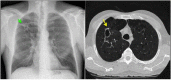

Non-tuberculous mycobacteria (NTM) are ubiquitous environmental organisms that may cause opportunistic infections in susceptible hosts. Lung infections in immunocompetent persons with structural lung disease are most common, while disseminated disease occurs primarily in immunocompromised individuals. Human disease caused by certain species, such as Mycobacterium avium complex, Mycobacterium abscessus, and Mycobacterium kansasii, is increasing in incidence and varies by geographic distribution. The spectrum of NTM disease varies widely in presentation and clinical outcome, but certain patterns can be organized into clinical phenotypes. Treatment options are limited, lengthy, and often toxic. The purpose of this case-based review is to provide non-clinician scientists with a better understanding of human NTM disease with an aim to stimulate more research and development.